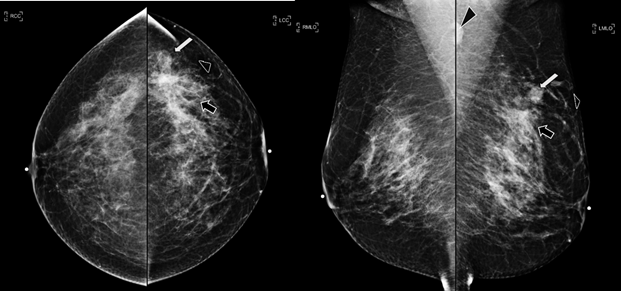

Figure 1 Craneocaudal and Mediolateral Oblique projections. The breast tissue is the heterogeneously dense (category “C” of the American College of Radiology, 2013). In the left breast, exists a focal asymmetry associated with residual cluster of amorphous microcalcifications and architectural distortion, localized in the middle third of the upper outer quadrant, that coincides with the site of the biopsy (black arrow). Adjacent to these findings, at the superior region, a new nodule is observed (white arrow). This nodule is isodense, round and with microlobulated margins, which corresponds to the palpable area which is signaling by radiolucent triangular tissue marker. In the ipsilateral axillary region, an anormal lymph node is seen (head arrow).